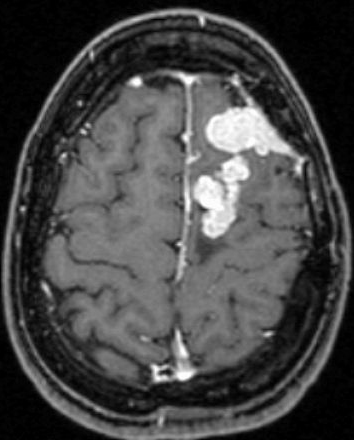

Tratamiento de Meningioma con Radiocirugía Estereotáxica. Paciente había sido operada a craéneo abierto en dos ocasiones, y viene por recurrencia del tumor

Resonancia magnética dos años después de la radiocirugía. Observe marcada y progresiva reducción del meningioma